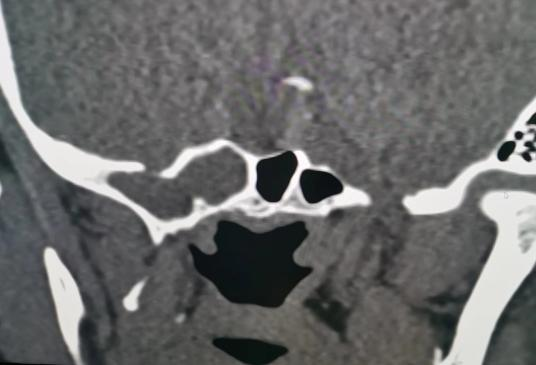

耳鼻咽喉头颈外科副主任医师宋建涛及主治医师王向锋、CT室主任刘康为患者进行详细影像学检查,确定脑脊液鼻漏的准确位置,同时积极完善鼻内镜等相关术前常规检查。6月3日为两位患者成功实施鼻内镜下脑膜脑膨出切除、脑脊液鼻漏阔筋膜修补术。经过精心护理,患者恢复良好,现均已出院。

据文献报道,脑脊液鼻漏是脑脊液通过颅底(颅前、中或后窝)或其它部位骨质缺损、破裂处流出,经过鼻腔,最终流出体外。主要表现为鼻腔间断或持续流出清亮、水样液体,鼻漏生化检查与脑脊液成分相符合。发病原因可分为创伤性和非创伤性,其中创伤性分为外伤性和医源性,非创伤性分为自发性、肿瘤性和先天性。两名患者均为自发性(又名原发性或特发性)脑脊液鼻漏,病因不明。最常见漏口部位为筛板,其次为蝶骨侧凹,可能因筛板或鞍底缺血萎缩,后被充满脑脊液的蛛网膜囊填充,脑脊液搏动性冲击颅底,进而侵袭局部骨质形成缺损,最终导致脑脊液鼻漏。